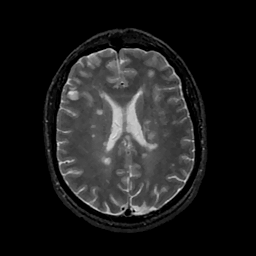

MR Study #11, May 5, 1991 -- Slice #31